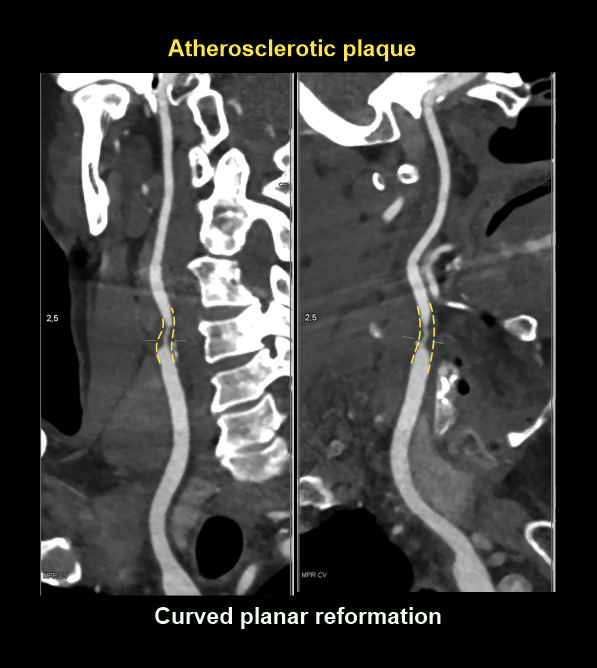

- Curved MPR images of arteries to clearly visualize atherosclerotic plaques.